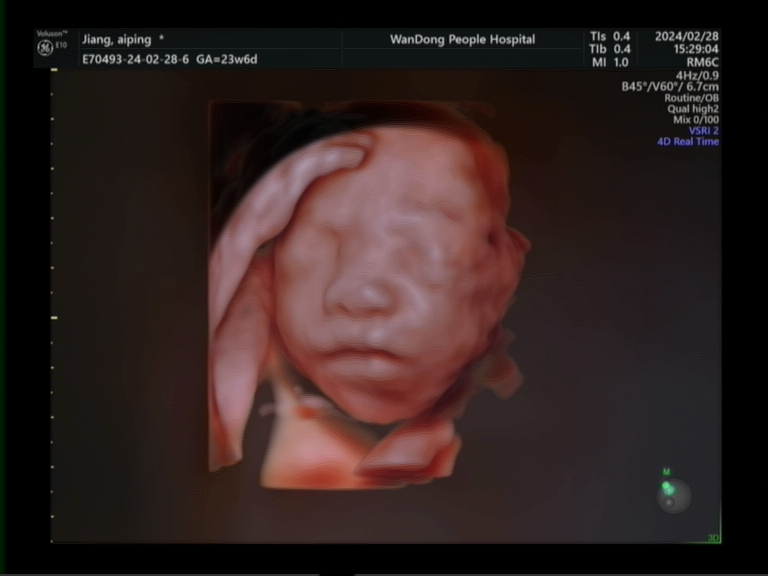

超聲科目前擁有多臺國內(nèi)、國際先進(jìn)的高檔彩色超聲診斷儀:GE-E10四維彩超、GE-E9、GE-S8、飛利浦iU22等,并配備床邊便攜式高檔超聲診斷儀飛利浦CX-50。儀器圖像清晰,分辨率高,各種專用探頭配備齊全,并采用超聲圖文工作站對報告及檔案實行信息化管理。

特色醫(yī)療:目前開展項目包括腹部、心臟、血管、婦產(chǎn)及淺表器官(甲狀腺、乳腺)、并開展腔內(nèi)彩超(經(jīng)陰道超聲檢查、經(jīng)直腸前列腺超聲檢查)等;近年來為了降低胎兒出生缺陷,提高生存質(zhì)量,提升診斷準(zhǔn)確性,開展了胎兒早孕期(NT)篩查、胎兒中孕期系統(tǒng)(四維)篩查、先天性小兒髖關(guān)節(jié)發(fā)育不良篩查、超聲引導(dǎo)下各臟器穿刺活檢等。同時我院為方便患者,開展了床旁超聲及24小時急診超聲服務(wù)。